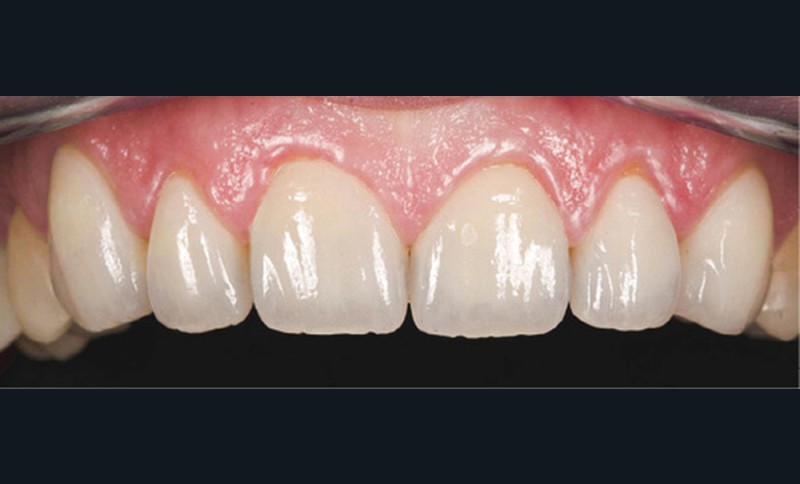

Ce mock-up est équilibré puis transformé en projet provisoire pour trois mois afin de s’assurer de la stabilité, du confort masticatoire et de l’esthétique. Au terme de ces trois mois, une empreinte de la situation est réalisée ainsi que l’enregistrement de l’occlusion ; enfin les secteurs postérieurs sont préparés pour recevoir des overlays. L’ensemble des informations (position et forme) est repris au sein du laboratoire pour dessiner les prothèses d’usage. Ces dernières seront produites par usinage, puis maquillées avant d’être envoyées au cabinet pour assemblage par collage sous champ opératoire (fig. 21 à 23).

Une fois les secteurs postérieurs et l’assise occlusale rétablis, le bloc incisivo-canin antérieur est préparé pour des restaurations adhésives. Là encore, l’assemblage se fait par collage sous champ opératoire. Le suivi est assuré pour contrôler la pérennité du traitement et une éventuelle reprise des usures. Pour ce faire, des rendez-vous cliniques avec réalisation d’une empreinte optique semestrielle sont programmés. La précision de l’empreinte permet ainsi de dépister le moindre phénomène d’usure (fig. 24 à 27).